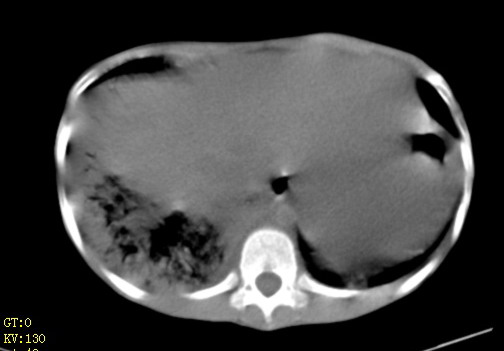

女,12岁,气促、咳嗽2天,3个月前查胸片示:两肺感染,急诊入院查ct,血常规等未检查。

左肺上叶改变考虑继发性肺结核,余双肺重症肺炎不排除h1n1。双侧胸腔少量积液。

1)考虑两肺感染性病变;建议抗炎治疗后复查。2)双侧少量胸腔积液。

1、左心房、左心室增大,考虑左心衰, 2、肺水肿合并感染 3、双侧胸腔积液

双肺中下野不规则片絮状阴影,中外带明显,双侧胸腔少量积液,心影增大,心腔密度减低,隆突下及左侧气管旁见钙化淋巴结影,考虑双肺感染、心衰;建议结合临床除外h1n1并急性心衰,先心不能排除。

两肺多发片絮状模糊影,以下肺外带居多,内见支气管气像,纵膈窗未减影,两侧胸腔积液,心影增大,结合心超,支持重症肺炎,非常时期,甲型h1n1流感不排除。